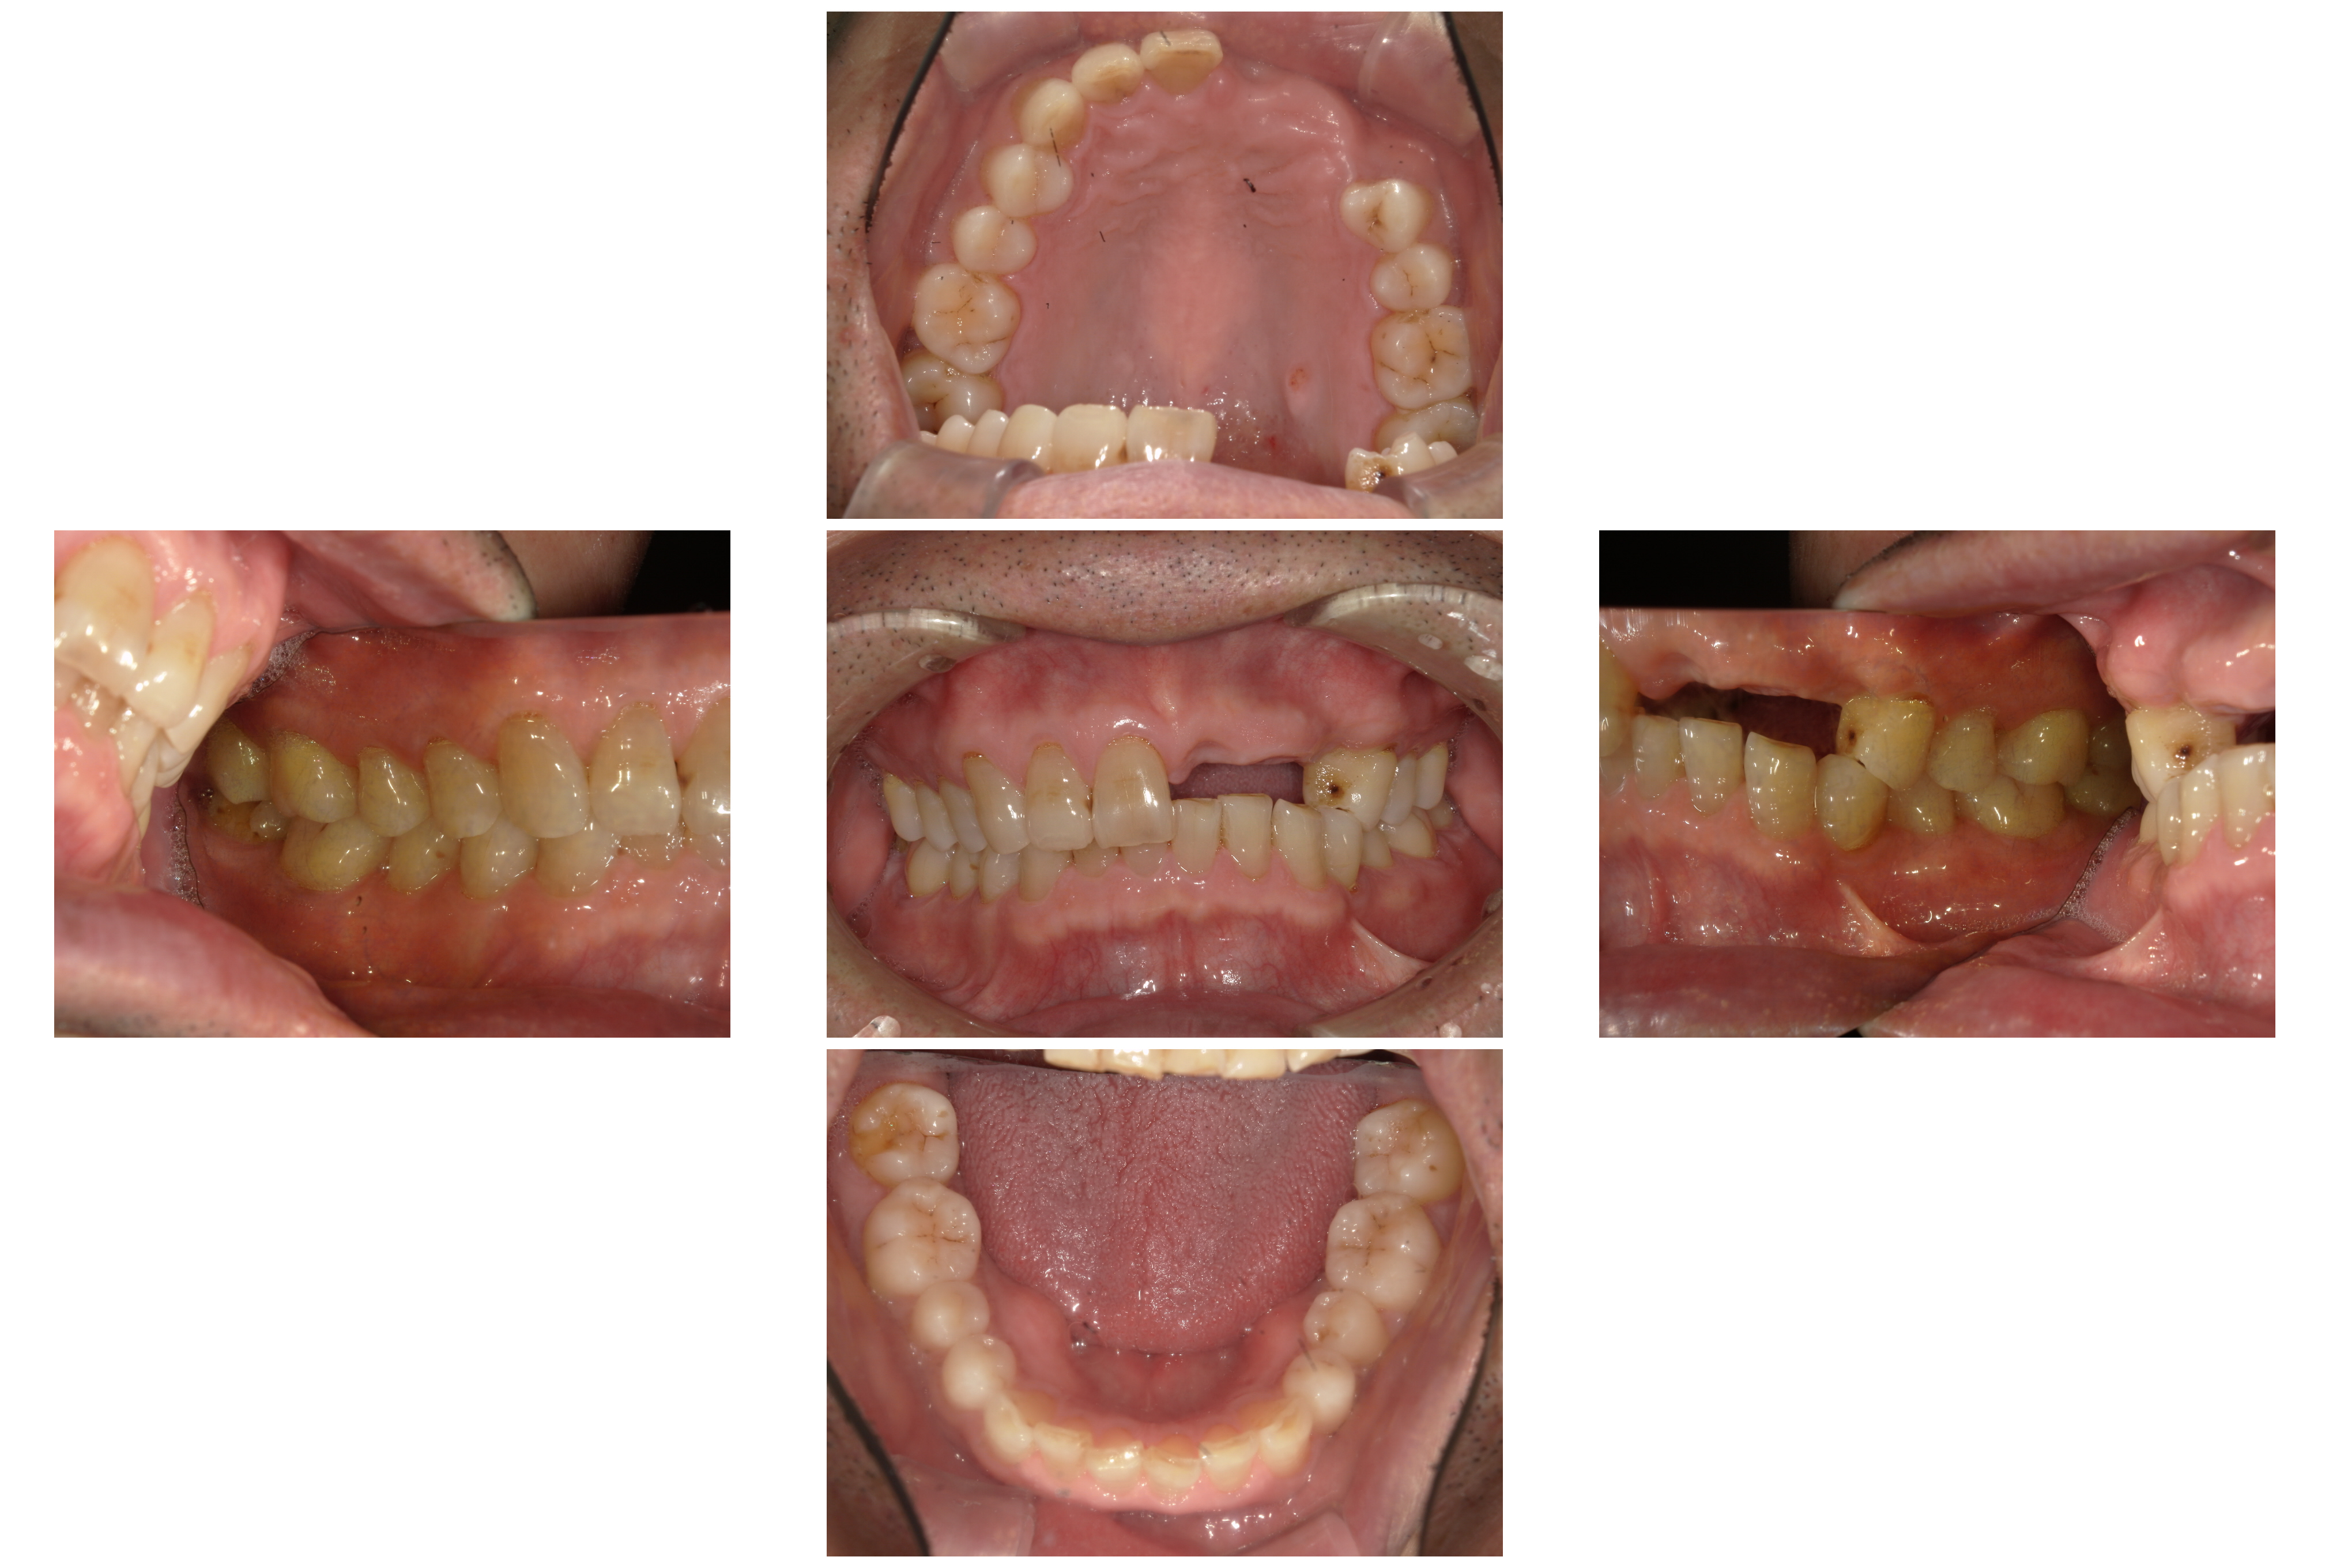

術前